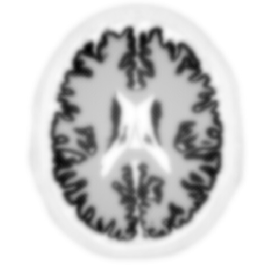

Non-TOF back-projection

TOF back-projection with 10ps FWHM CTR

Hoffman brain phantom simulated analytically without noise (courtesy: Johan Nuyts, University of Leuven).